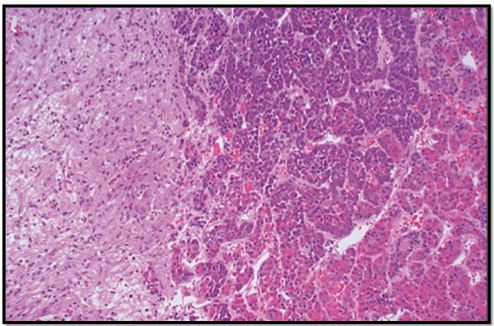

Q

identify tissue

A

normal pituitary

21

pituitary adenoma

22

histology features of pituitary adenoma

• monomorphism of cells

• absence of normal acinar architecture